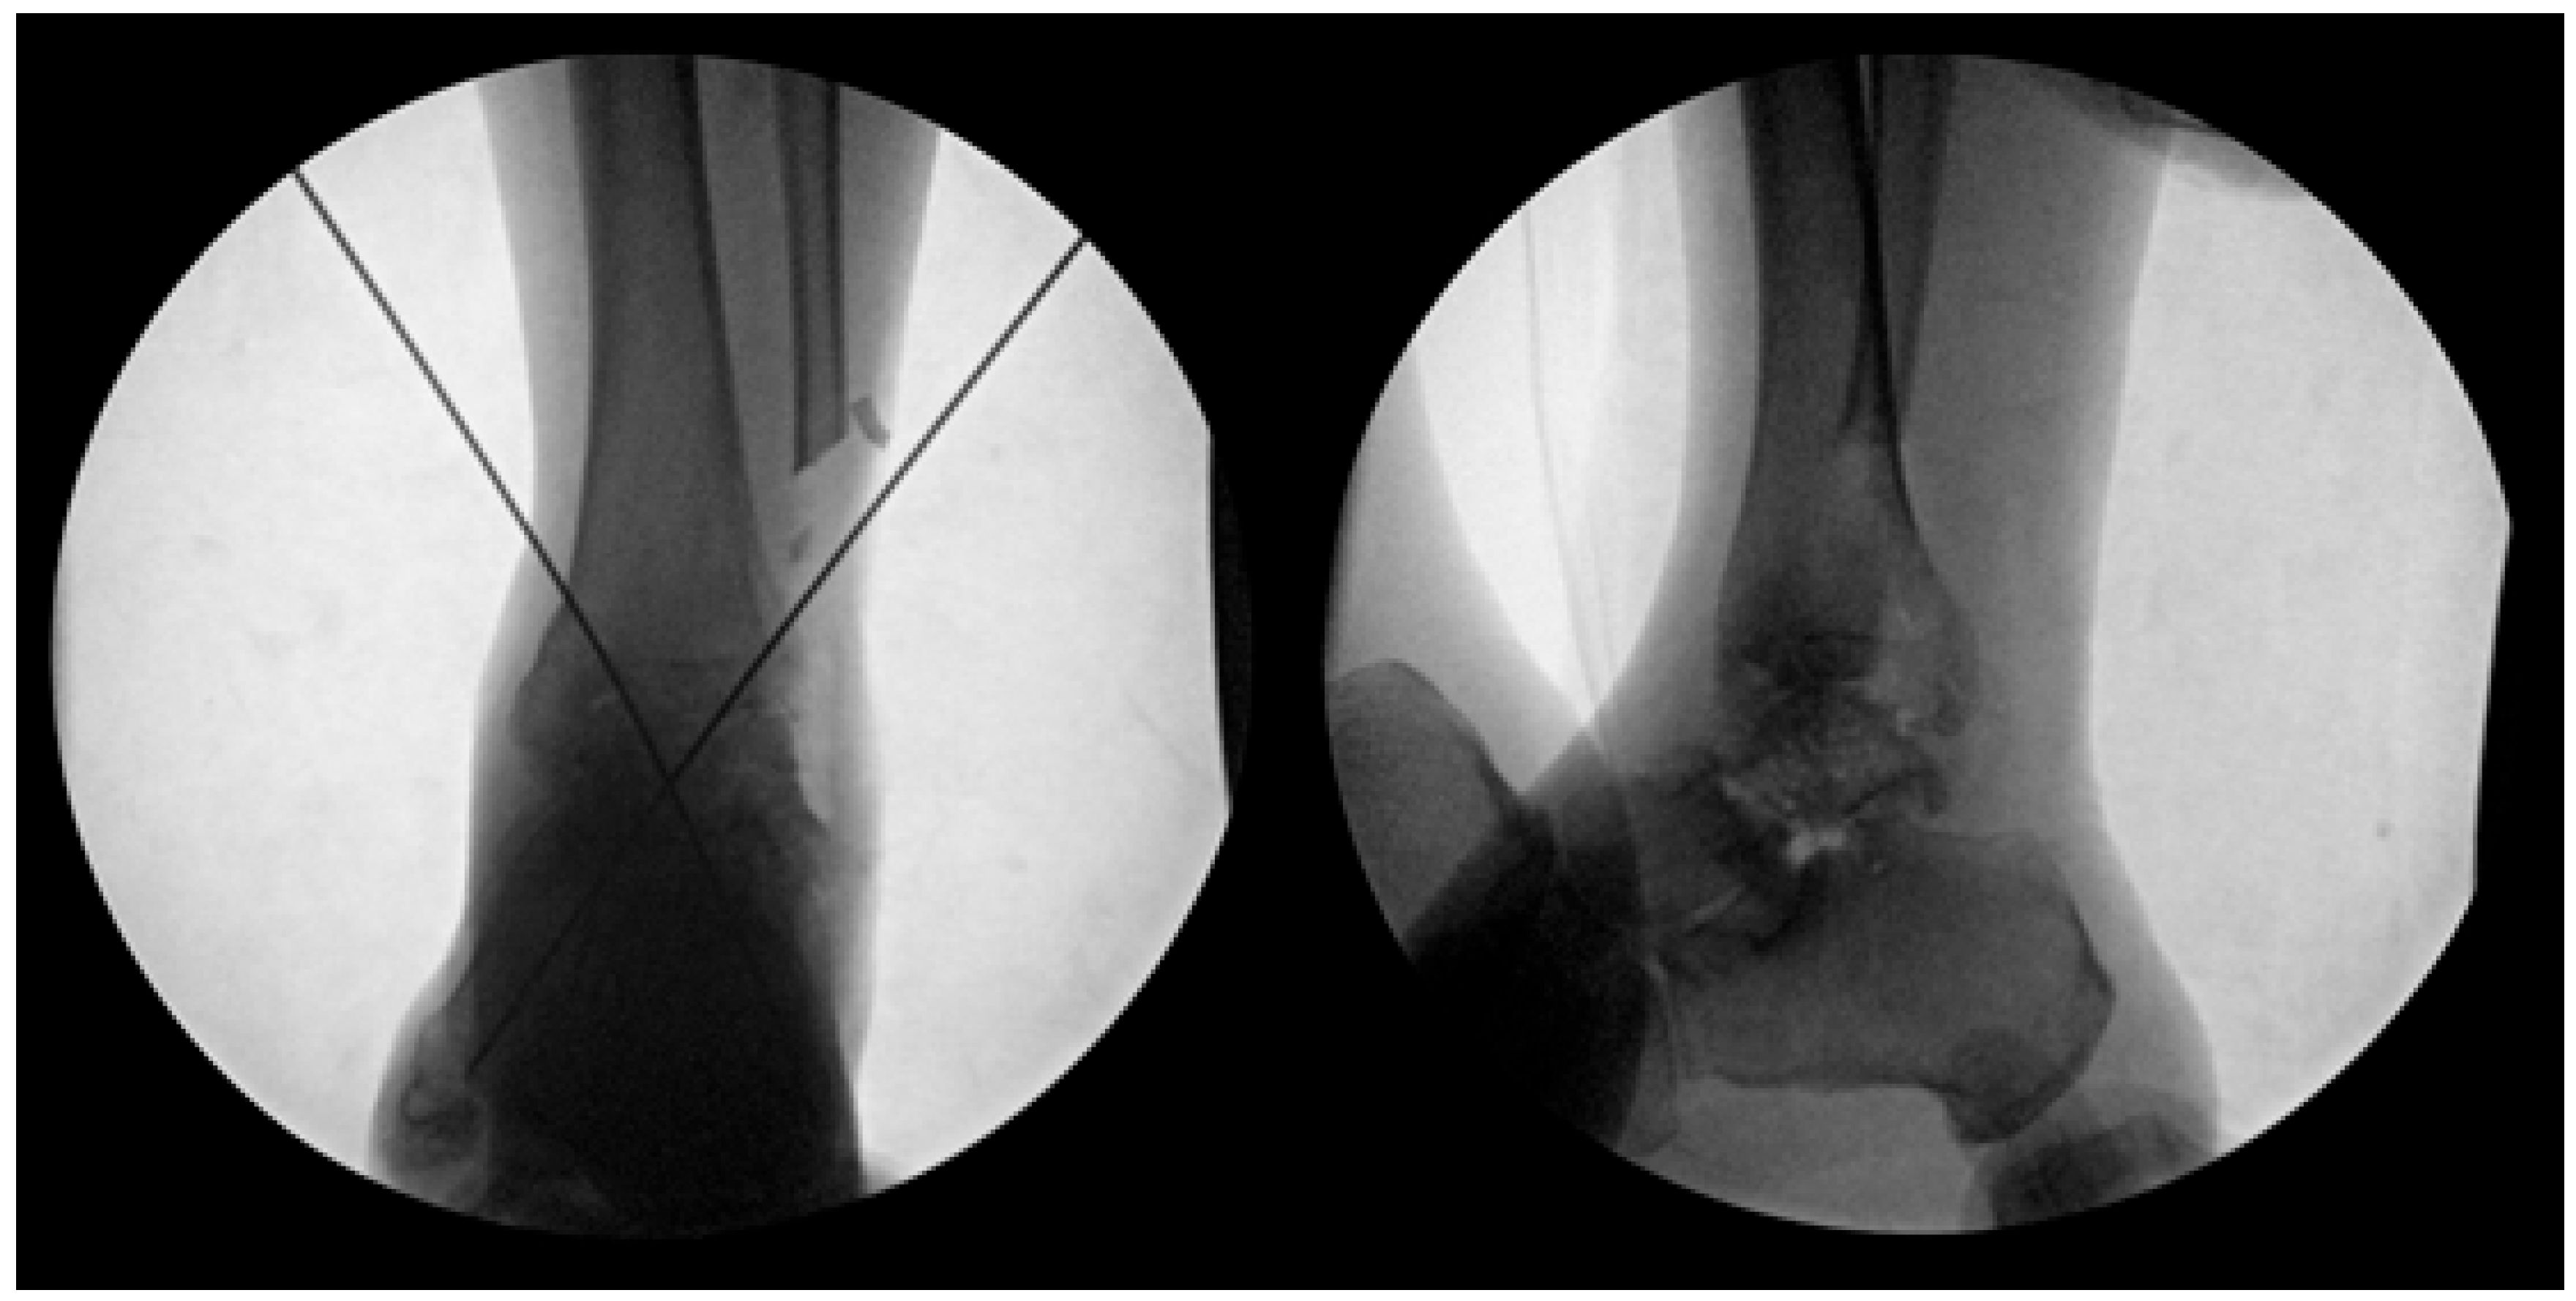

Preoperative surgical planning was initiated through detailed CT and plain radiographic evaluation of the contralateral, unaffected talus to determine the most appropriate size and shape of the allograft. This templating process included measurement of the maximum vertical height from the apex of the talar dome to the posterior facet (on the lateral view), the anteroposterior length of the talar head (on the superior view), and the maximal mediolateral width (Figure 1). These dimensions were used to estimate the optimal talar geometry. Additionally, patient-specific factors such as body height, body mass, and limb laterality were considered to enhance size matching accuracy. These preoperative measurements were then compared against a catalog of available cadaveric talus allografts from the national tissue bank to identify a suitable donor match. Once selected, the appropriate-sized fresh–frozen talus allograft was reserved and procured for intraoperative use. As of 2023, the cost of an allogeneic talus through the Korea Public Tissue Bank is approximately EUR 400, whereas, a femoral head allograft suitable for talar reconstruction costs approximately EUR 480.

Figure 1. Preoperative measurements were performed using standard radiographs of the contralateral, unaffected talus to guide selection of an appropriately sized allograft. Key anatomical dimensions include: (L) mediolateral width measured across the talar body in the superior view; (W) anteroposterior length from the talar head to the posterior margin in the superior view; (H) maximum vertical height from the apex of the talar dome to the posterior facet in the lateral view. These measurements were used to select the most anatomically compatible allograft from the national tissue bank for each patient.